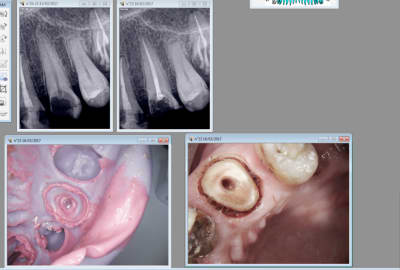

20/03/2017 à 09h54

Celle la ca saignait un peu. -)

Il faudrait que j'arrete de préparer trop sous gingival. Un réflexe à perdre.

Capture d écran 2017 03 20 09.49 - Eugenol

Tiens suite de mon Ic à 4 pattes empreinte prise le 9 03 et pose aujourd'hui. Aspect de la gencive encourageant après le coup de laser.